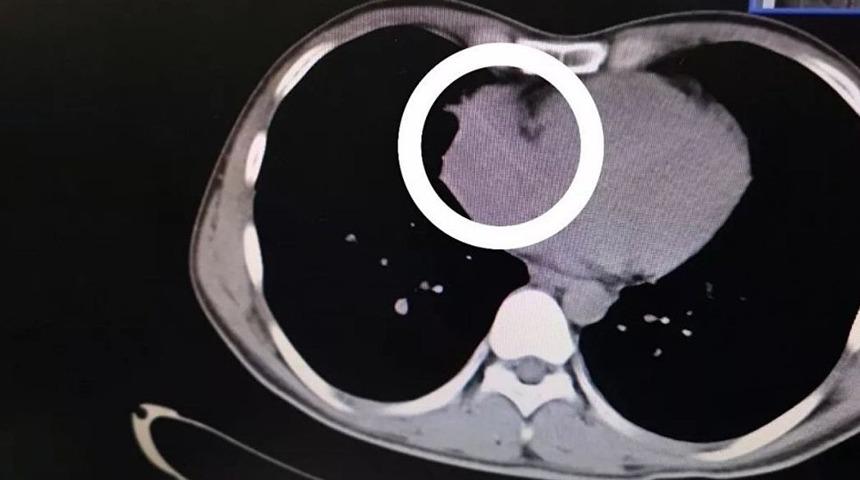

Çin'de doktorlar bir hastanın kalp atışlarındaki dengesizliği araştırırken, tesadüf eseri sağ kalp kapakçığında sivri uçlu bir nesne tespit etti. Hasta, kendi bardağını diğerlerinden ayırt edebilmek için her daim içine bir kürdan koyduğunu, muhtemelen onu yutmuş olabileceğini açıkladı.

Doktorlar, 29 yaşındaki Zhou soyadlı hastanın kalbinin sağ kapakçığında 6 santim uzunluğunda bir kürdan bulduklarını açıkladı. Kürdanın hastanın nefes yolundan geçip sağ ciğerini delerek, kalbe ulaştığı düşünülüyordu. Yedi saatlik bir operasyonun ardından hastanın durumu kontrol altına alındı.

Tetkiklerin ardından doktorlar, Zhou'nun sağ ciğerinde anormal bir gölge ve sağ kalp kapakçığında aşırı bir genişleme tespit ettiler. Genişlemeyi önlemek üzere açık kalp ameliyatına başladıklarında ise, onları kalbe saplanmış bir kürdan karşıladı.